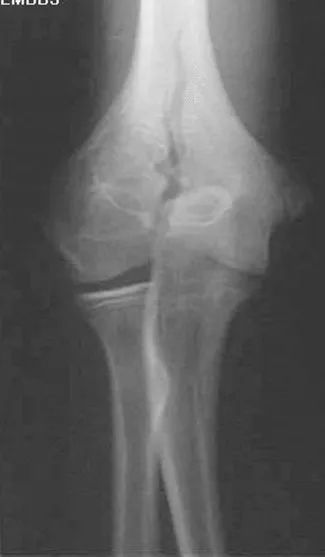

肱骨髁间骨折

疼痛科怎么理疗疼痛科医生、康复理疗科医生、针刀针灸医生应掌握的常见骨科疾病X光片_https://www.jmylbn.com_新闻资讯_第13张